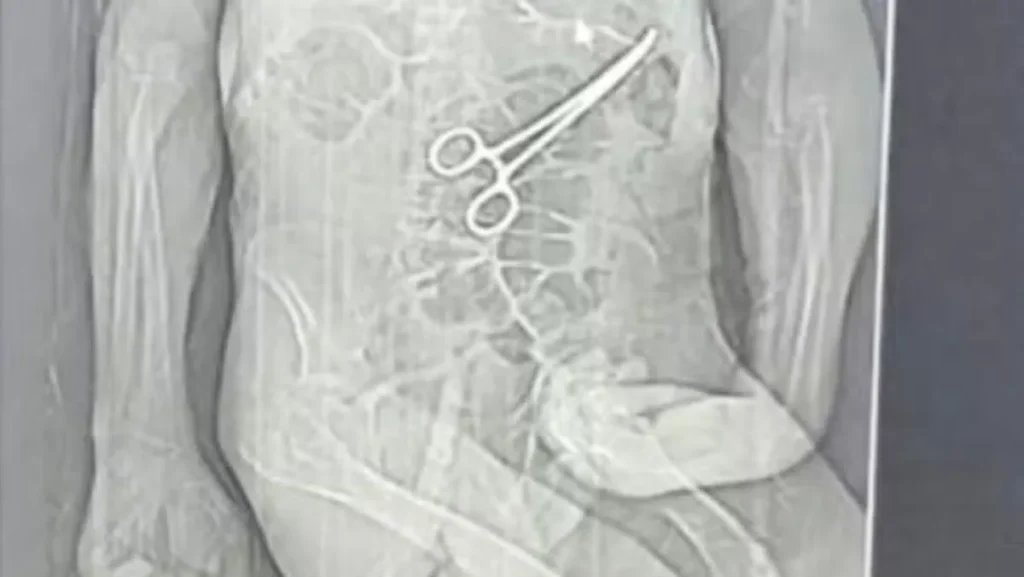

A família de Manoel tomou conhecimento da situação através de um exame de tomografia que foi divulgado por uma rádio local. Esse exame indicava a presença do instrumento cirúrgico esquecido no corpo do idoso. O advogado que representa a família confirmou que as medidas legais começaram a ser tomadas após essa revelação, uma vez que a informação só veio à tona após o falecimento de Manoel.

De acordo com os familiares, o fato de a pinça cirúrgica ter permanecido no corpo do paciente após a primeira cirurgia foi um detalhe alarmante que surpreendeu a todos. Manoel Cardoso de Brito faleceu no dia 24 de dezembro, e a dor da perda se agravou com a descoberta da negligência médica.